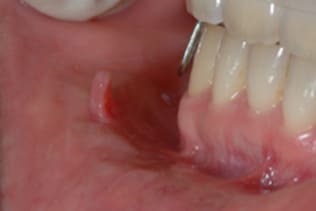

症例6 頬粘膜腫瘍(線維腫)の手術(40歳代 女性)

右側の頬にできものができ治らないので当クリニックを受診された。

右側頬粘膜に境界明瞭な弾性硬の腫瘍を認め、線維腫を疑い腫瘍摘出術を施行した。

局所浸潤麻酔を行い、腫瘍に糸をかけ、十分にカウンタートラクションをかけた状態で、腫瘍の境界に沿ってメスで上皮を木の葉状に切開し、牽引しながらメスで周囲の結合組織と腫瘍の境界を鋭利に剥離する。切る感じではなくて削ぐ感じでメスを用いることが重要である。